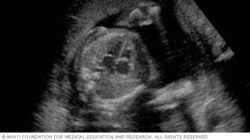

During a fetal ultrasound, a device called a transducer is placed on the pregnant person's belly. Or in some cases, it may be placed in the vagina or on the area between the vagina and the anus. Sound waves are translated into a pattern of light and dark areas. That creates an image of the fetus on a screen, as shown below.

The image below shows a fetus's profile at 11 weeks of pregnancy, which is nine weeks after conception. At this stage, the head makes up about half of a fetus's length.